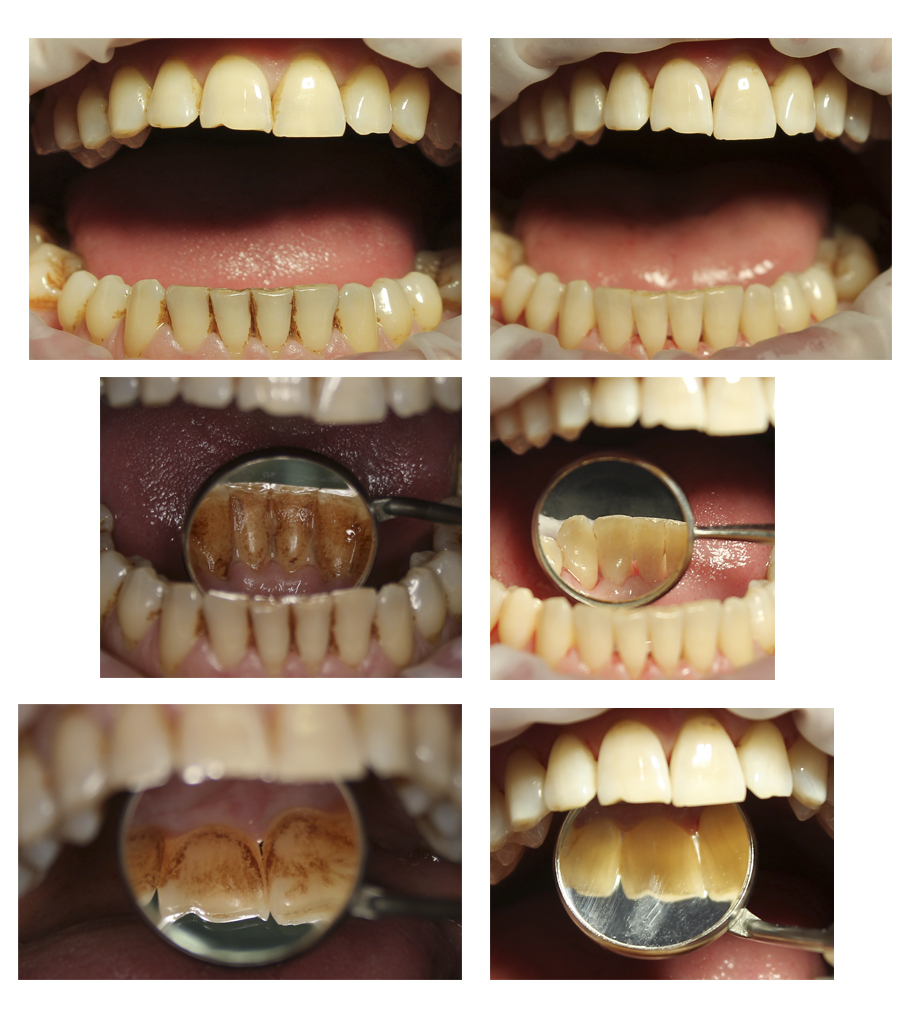

Прикорневой кариес: фото до и после